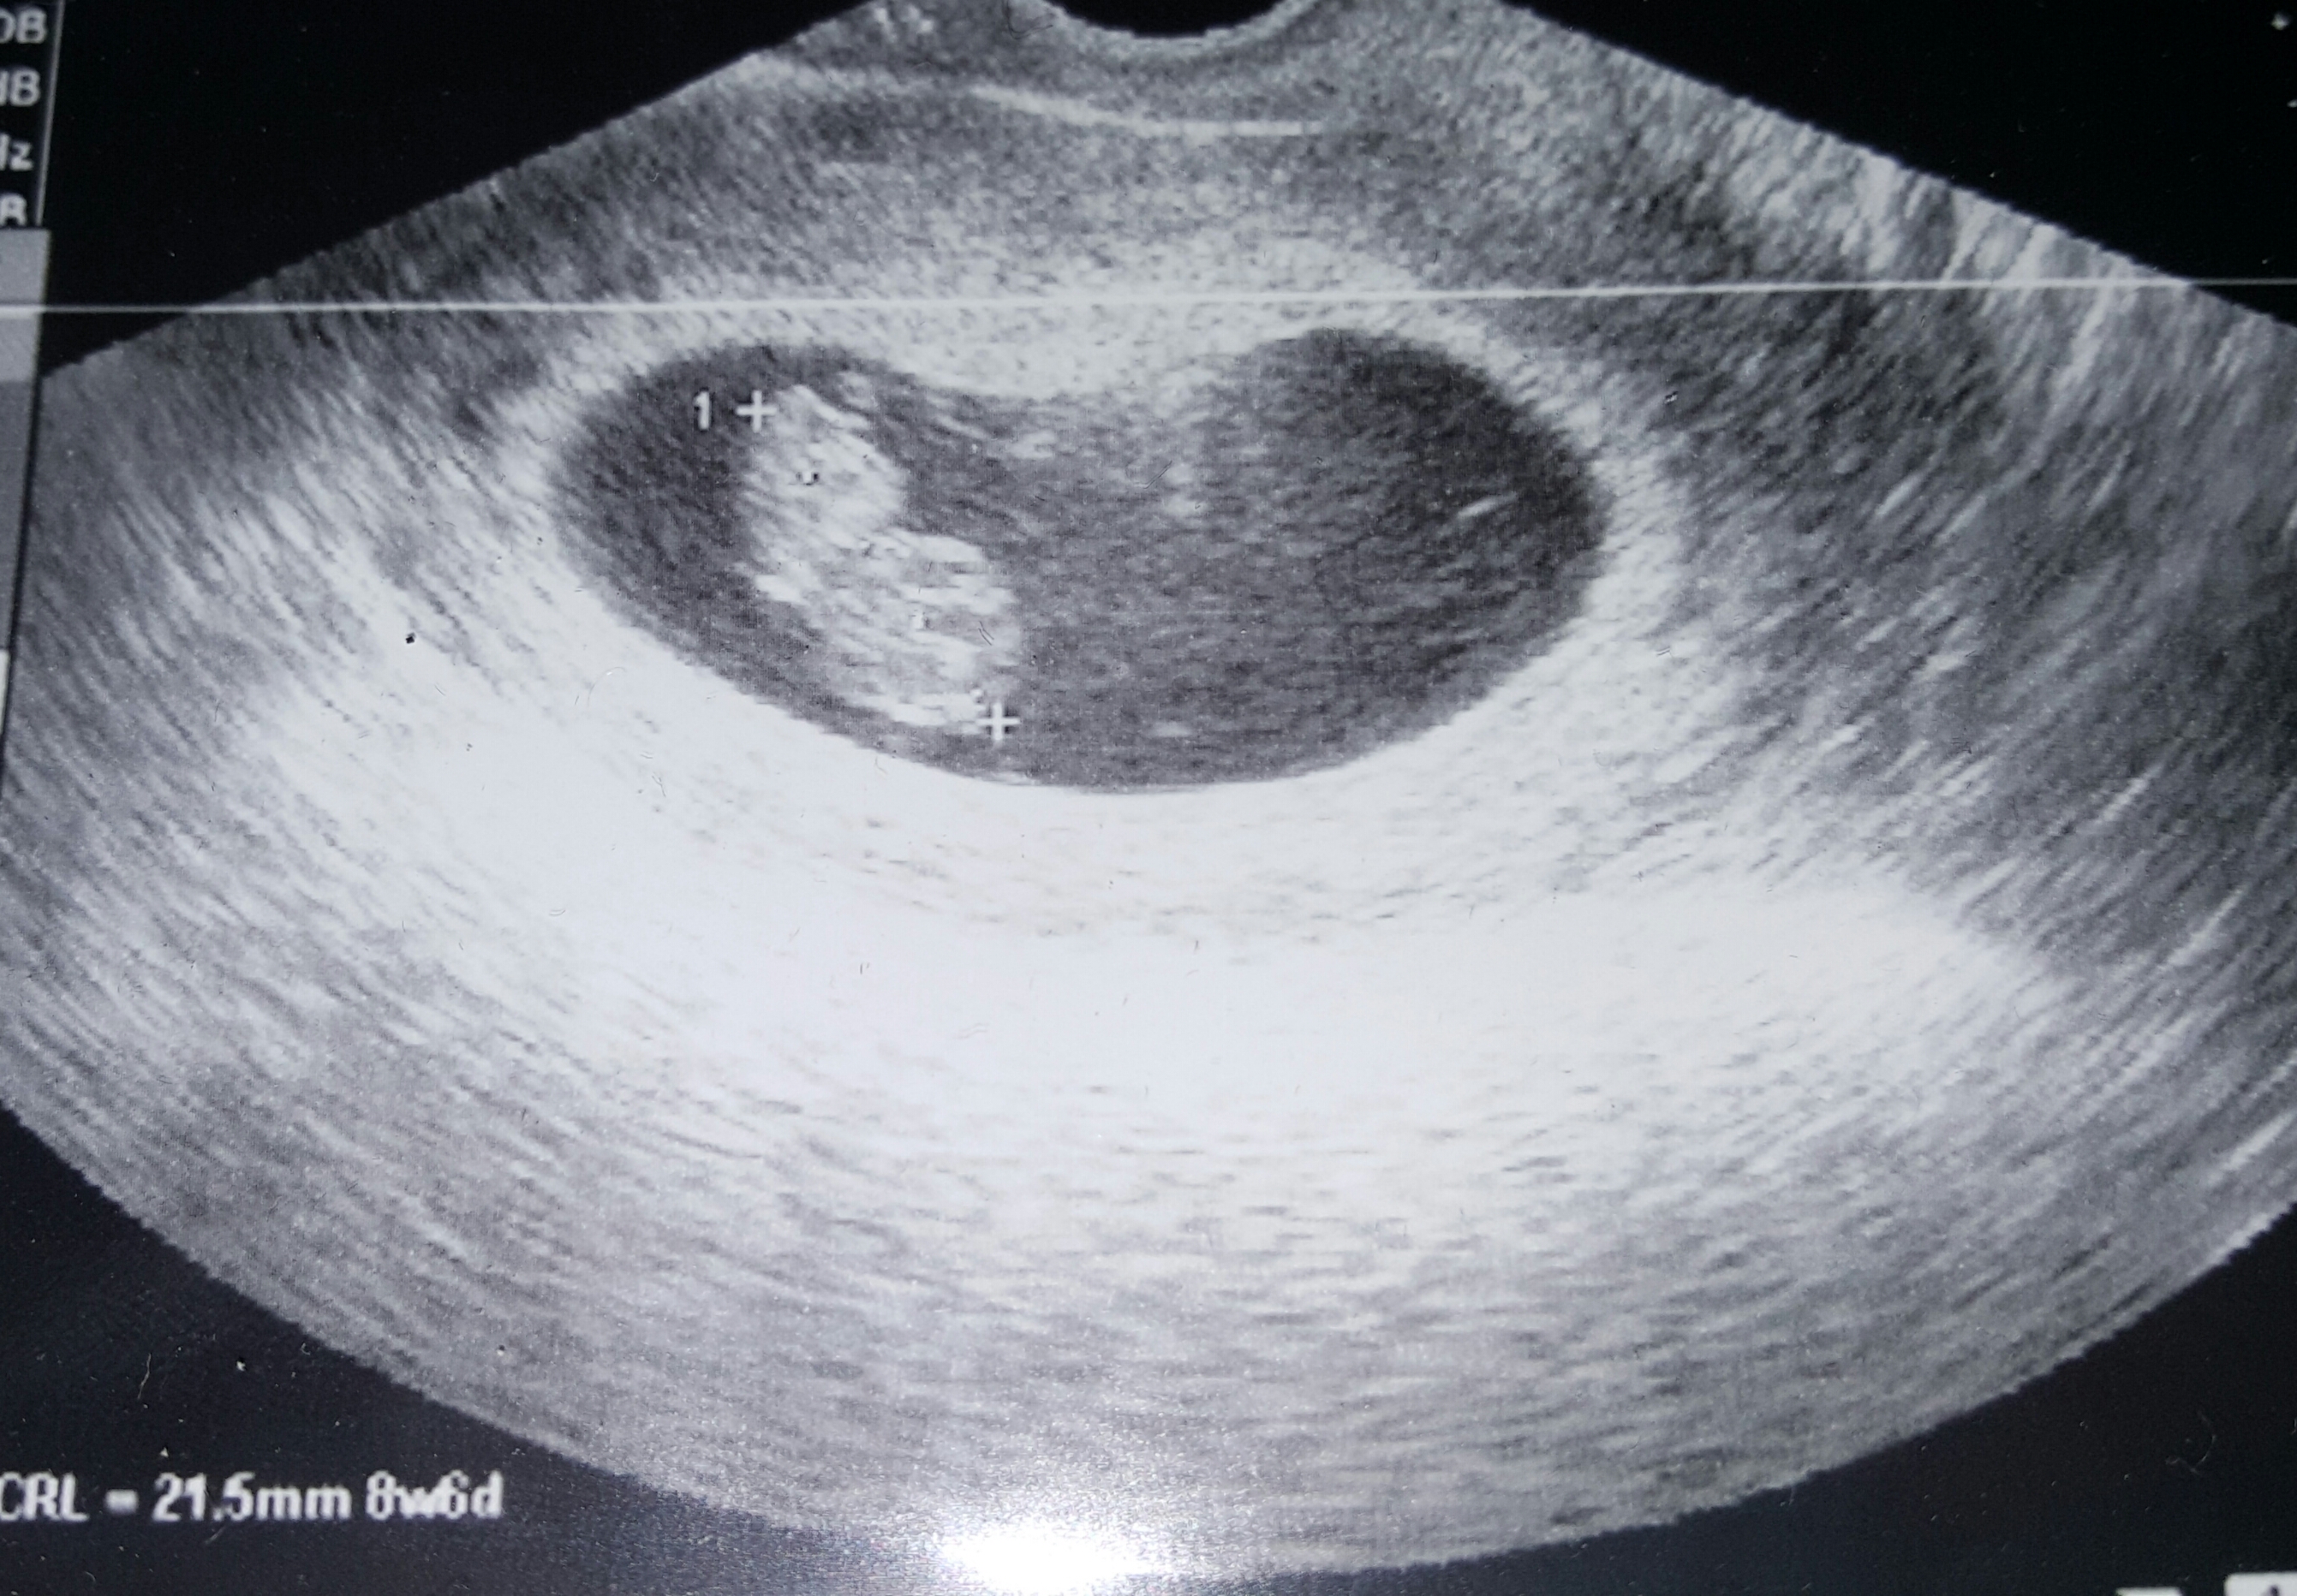

Had our first appointment yesterday. Baby measured right on track at 9w1d with a due date of May 10th! Very grateful that everything is going well so far.

Im 8wks today and went for my first ever ultrasound after 2 mc. It was great. I was measuring around 9wks though, which is also a plus! We got to hear the strong heart beat and see it wiggle around! It is just so amazingwhat our bodies do!